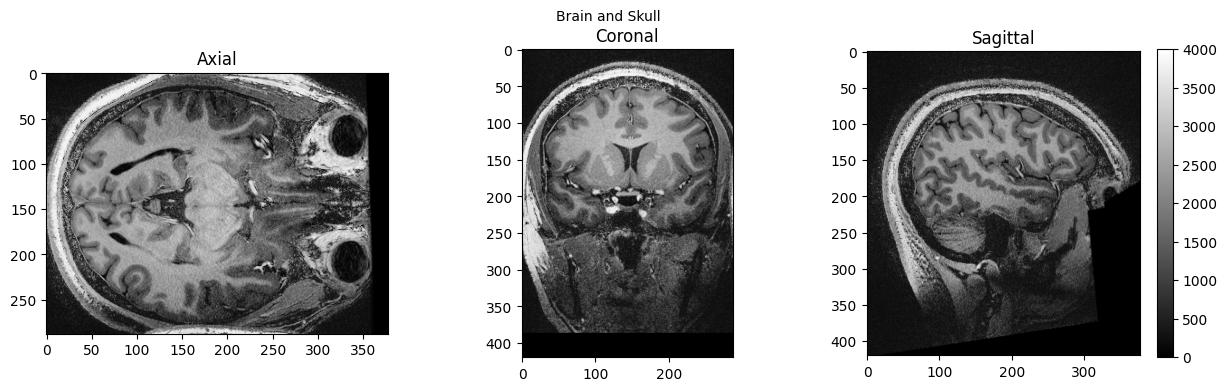

view_slices_3d(brain_full, slice_nbr=230, vmin=0, vmax=4000, title='Brain and Skull')